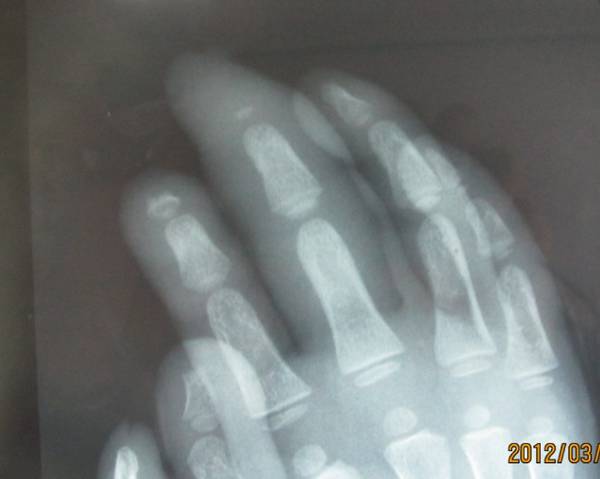

门诊的一个小患者。

双手反复感染。

自己咬伤。

可怜的孩子。

患儿,2岁9月。

说话不利,反应较同龄幼儿慢。

做肌电图时,针刺未哭闹。